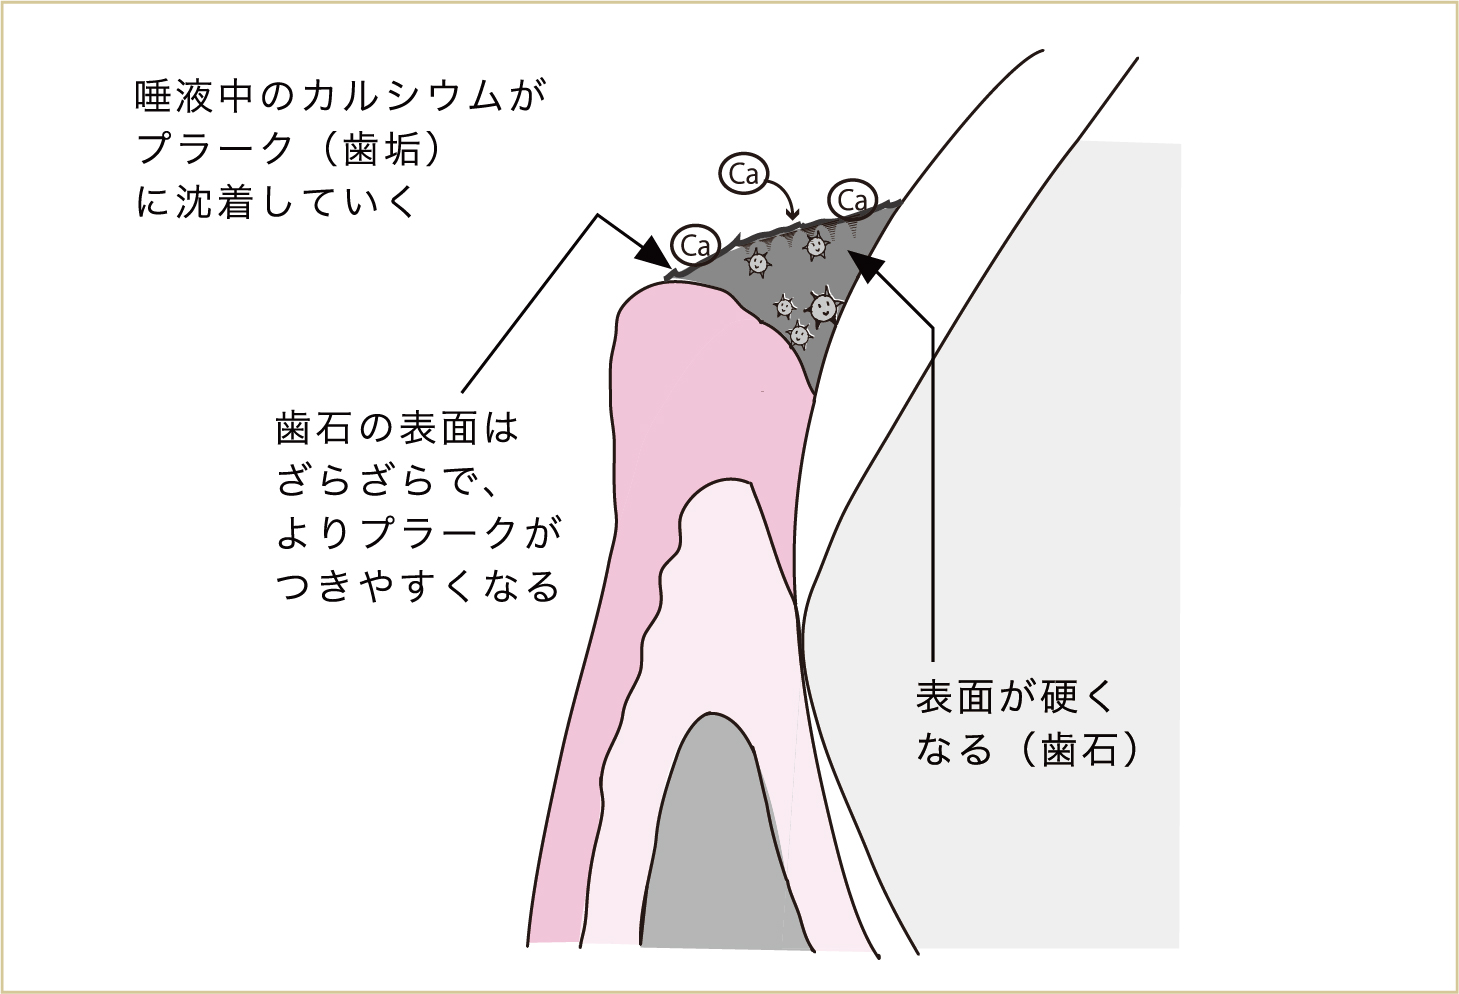

汚れが重なってくると、その表層には唾液中のカルシウムなどが沈着して硬くなっていきます。これが「歯石」で、この歯石の状態になってしまうと、歯ブラシでみがいてもとれなくなってしまいます。このような状態になる前に対処することが大切なのです。

いつも同じ所にみがき残しがあると、その表面に唾液中のカルシウムなどが沈着して硬くなってしまう(これが歯石)。